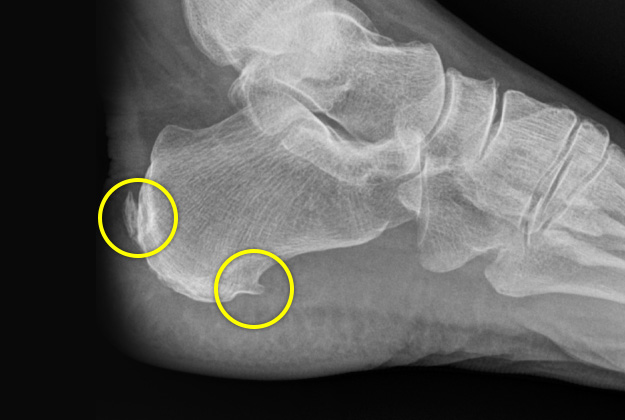

아킬레스건 또는 족저근막의 부착부위에 골극이 발생할 수 있습니다.

이는 치료의 대상이라기보다는 질병이 오래되었을 경우 발생하는 현상에 가깝습니다.

자꾸 당겨져서 생기기 때문에 견인성 골극이라고 합니다.